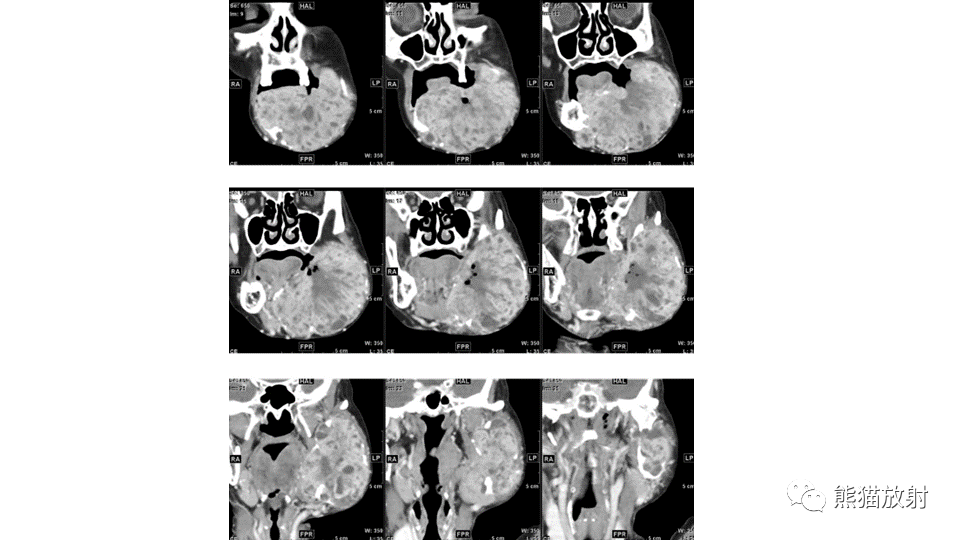

【病例】下颌骨成釉细胞瘤2例CT-1

【病例】下颌骨成釉细胞瘤2例CT-2

【病例】下颌骨成釉细胞瘤2例CT-3